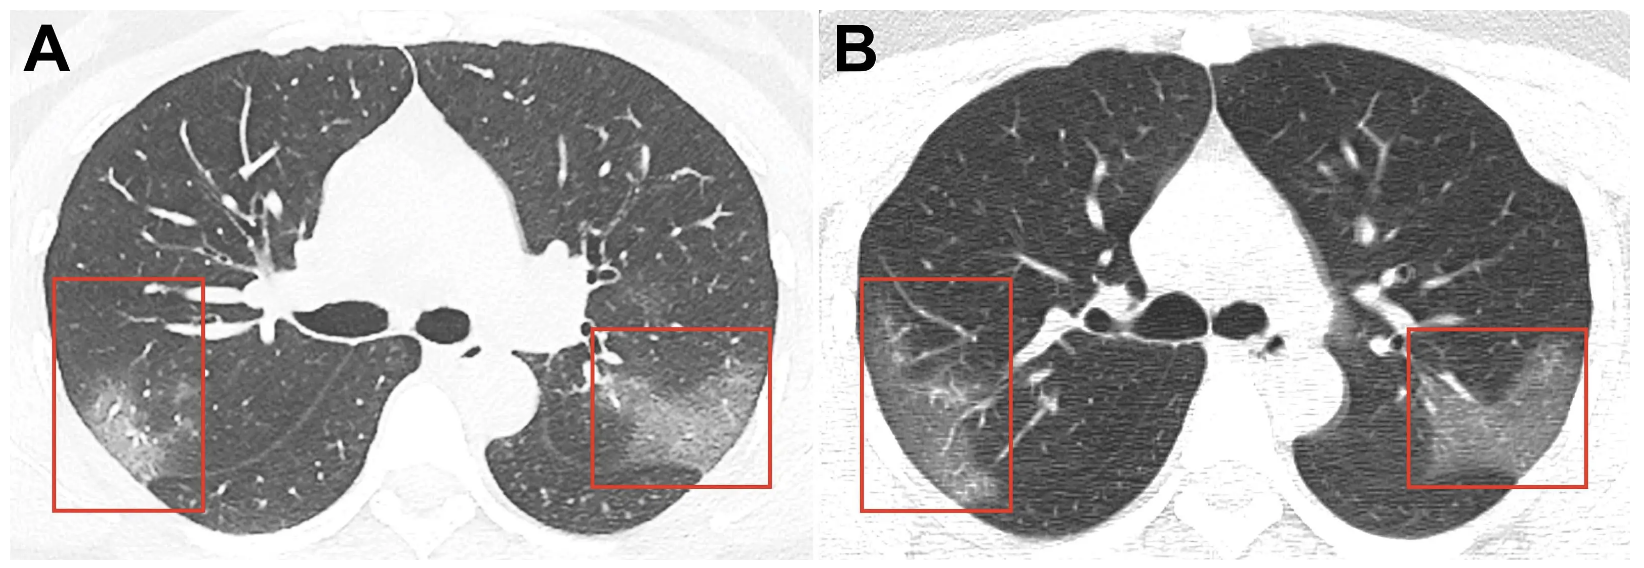

Өвчний урт хугацааны үр нөлөөг тогтооход арай эрт байгаа ч есөн өвчтөний уушгийг дурандахад цантсан шилтэй төстэй хэлбэрийн зүйл илэрчээ. Энэ нь уушгинд ямар нэгэн асуудал гарсныг илтгэж буй юм.